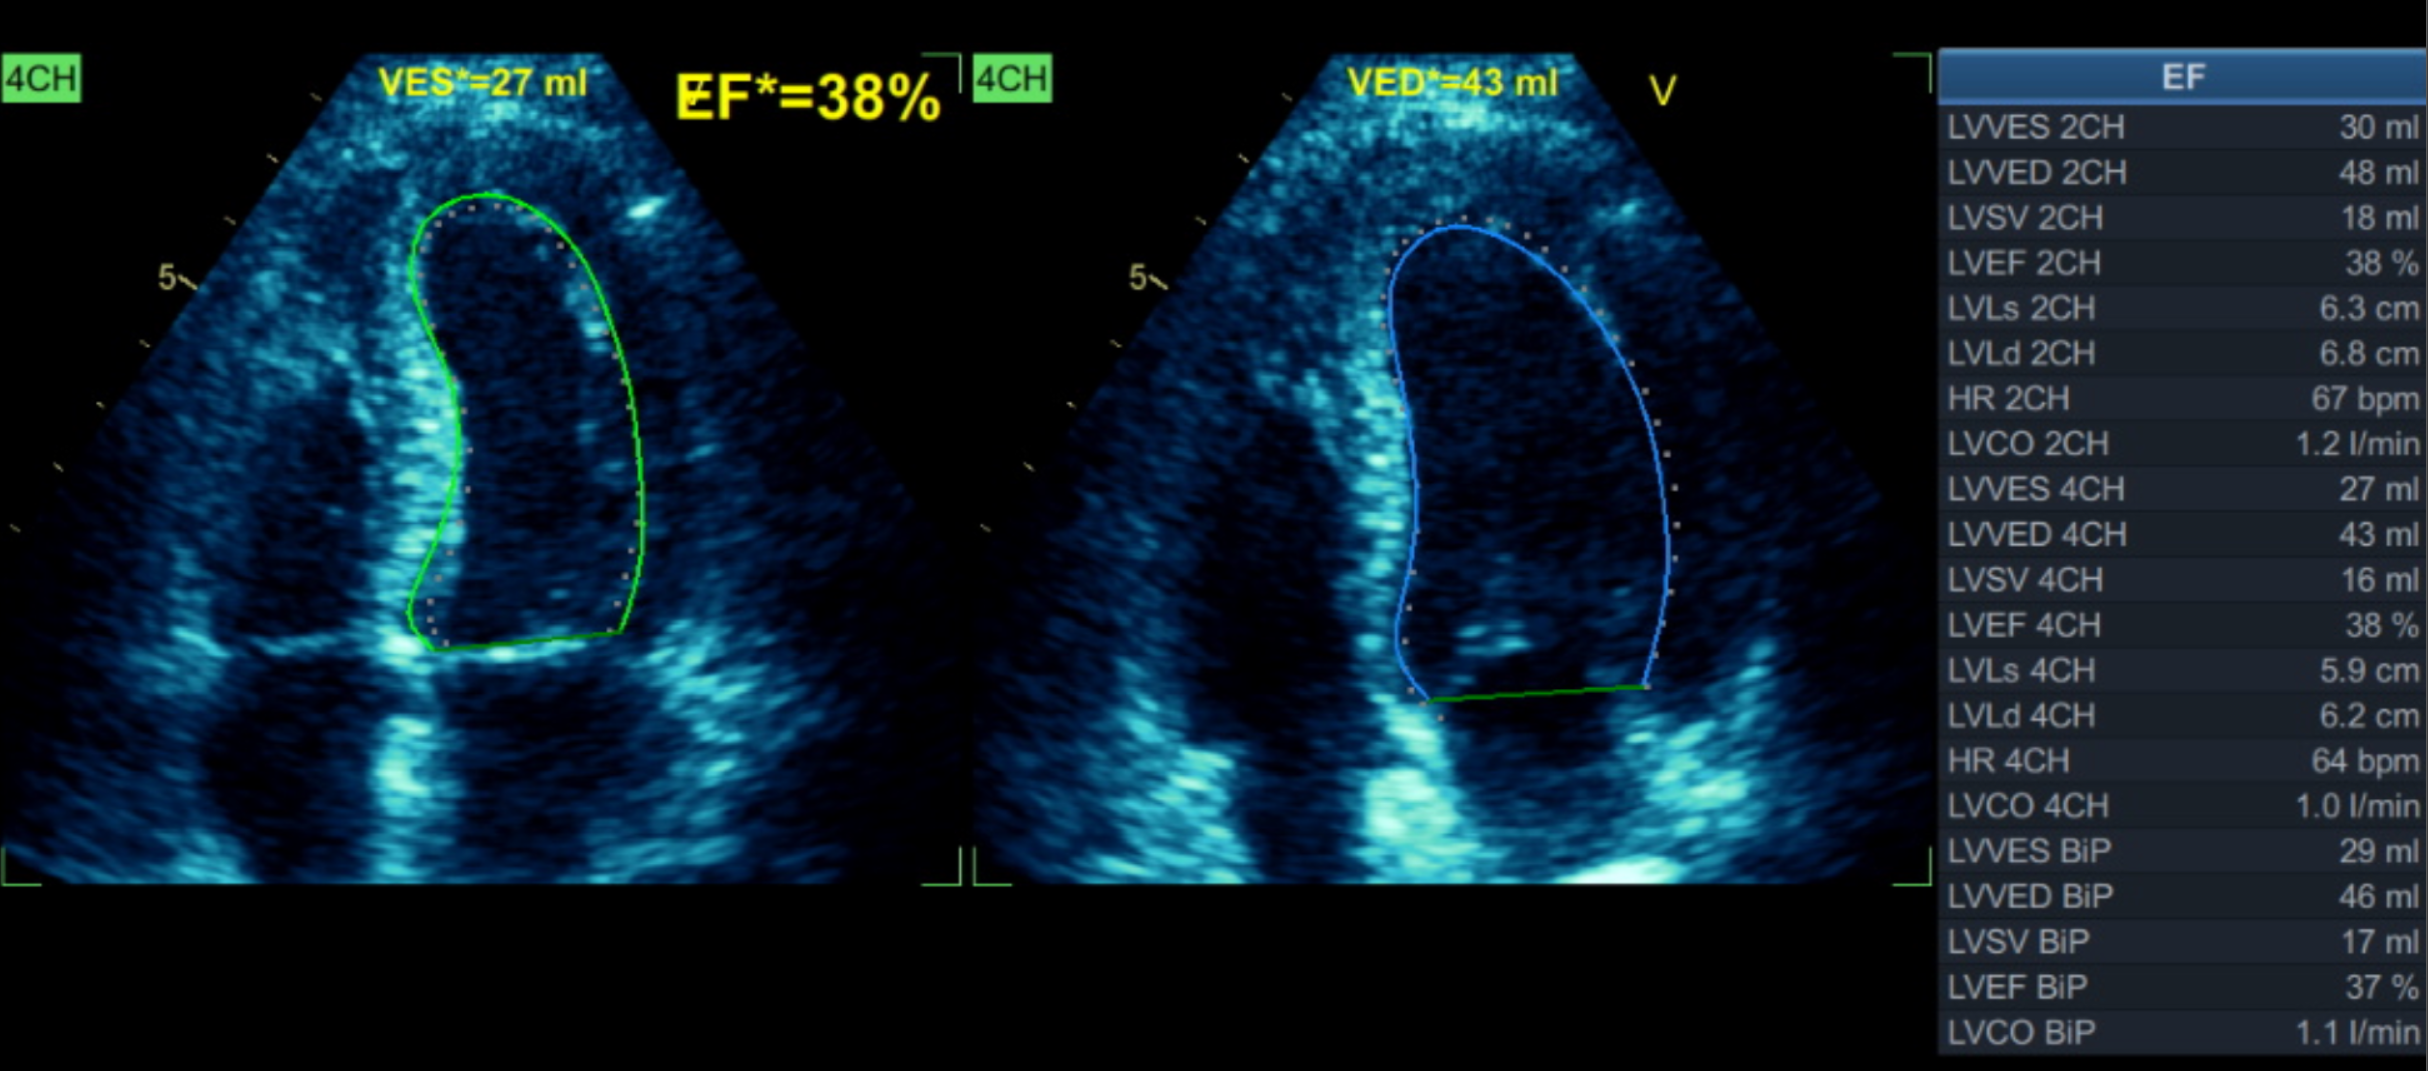

Relevant Test Results Prior to Catheterization

The initial angiogram on July 3rd, 2025, showed two-vessel coronary artery disease, with diffuse atherosclerosis extending from the proximal to distal LAD and moderate stenosis of the OM2. The RCA was absent and appeared to be supplied by the D1 branch, which showed severe disease at the ostium and mid segment. A repeat angiogram showed drop of blood flow with TIMI 2 flow to the distal LAD and RCAterritories. Then we proceed to PCI to LAD and RCA.